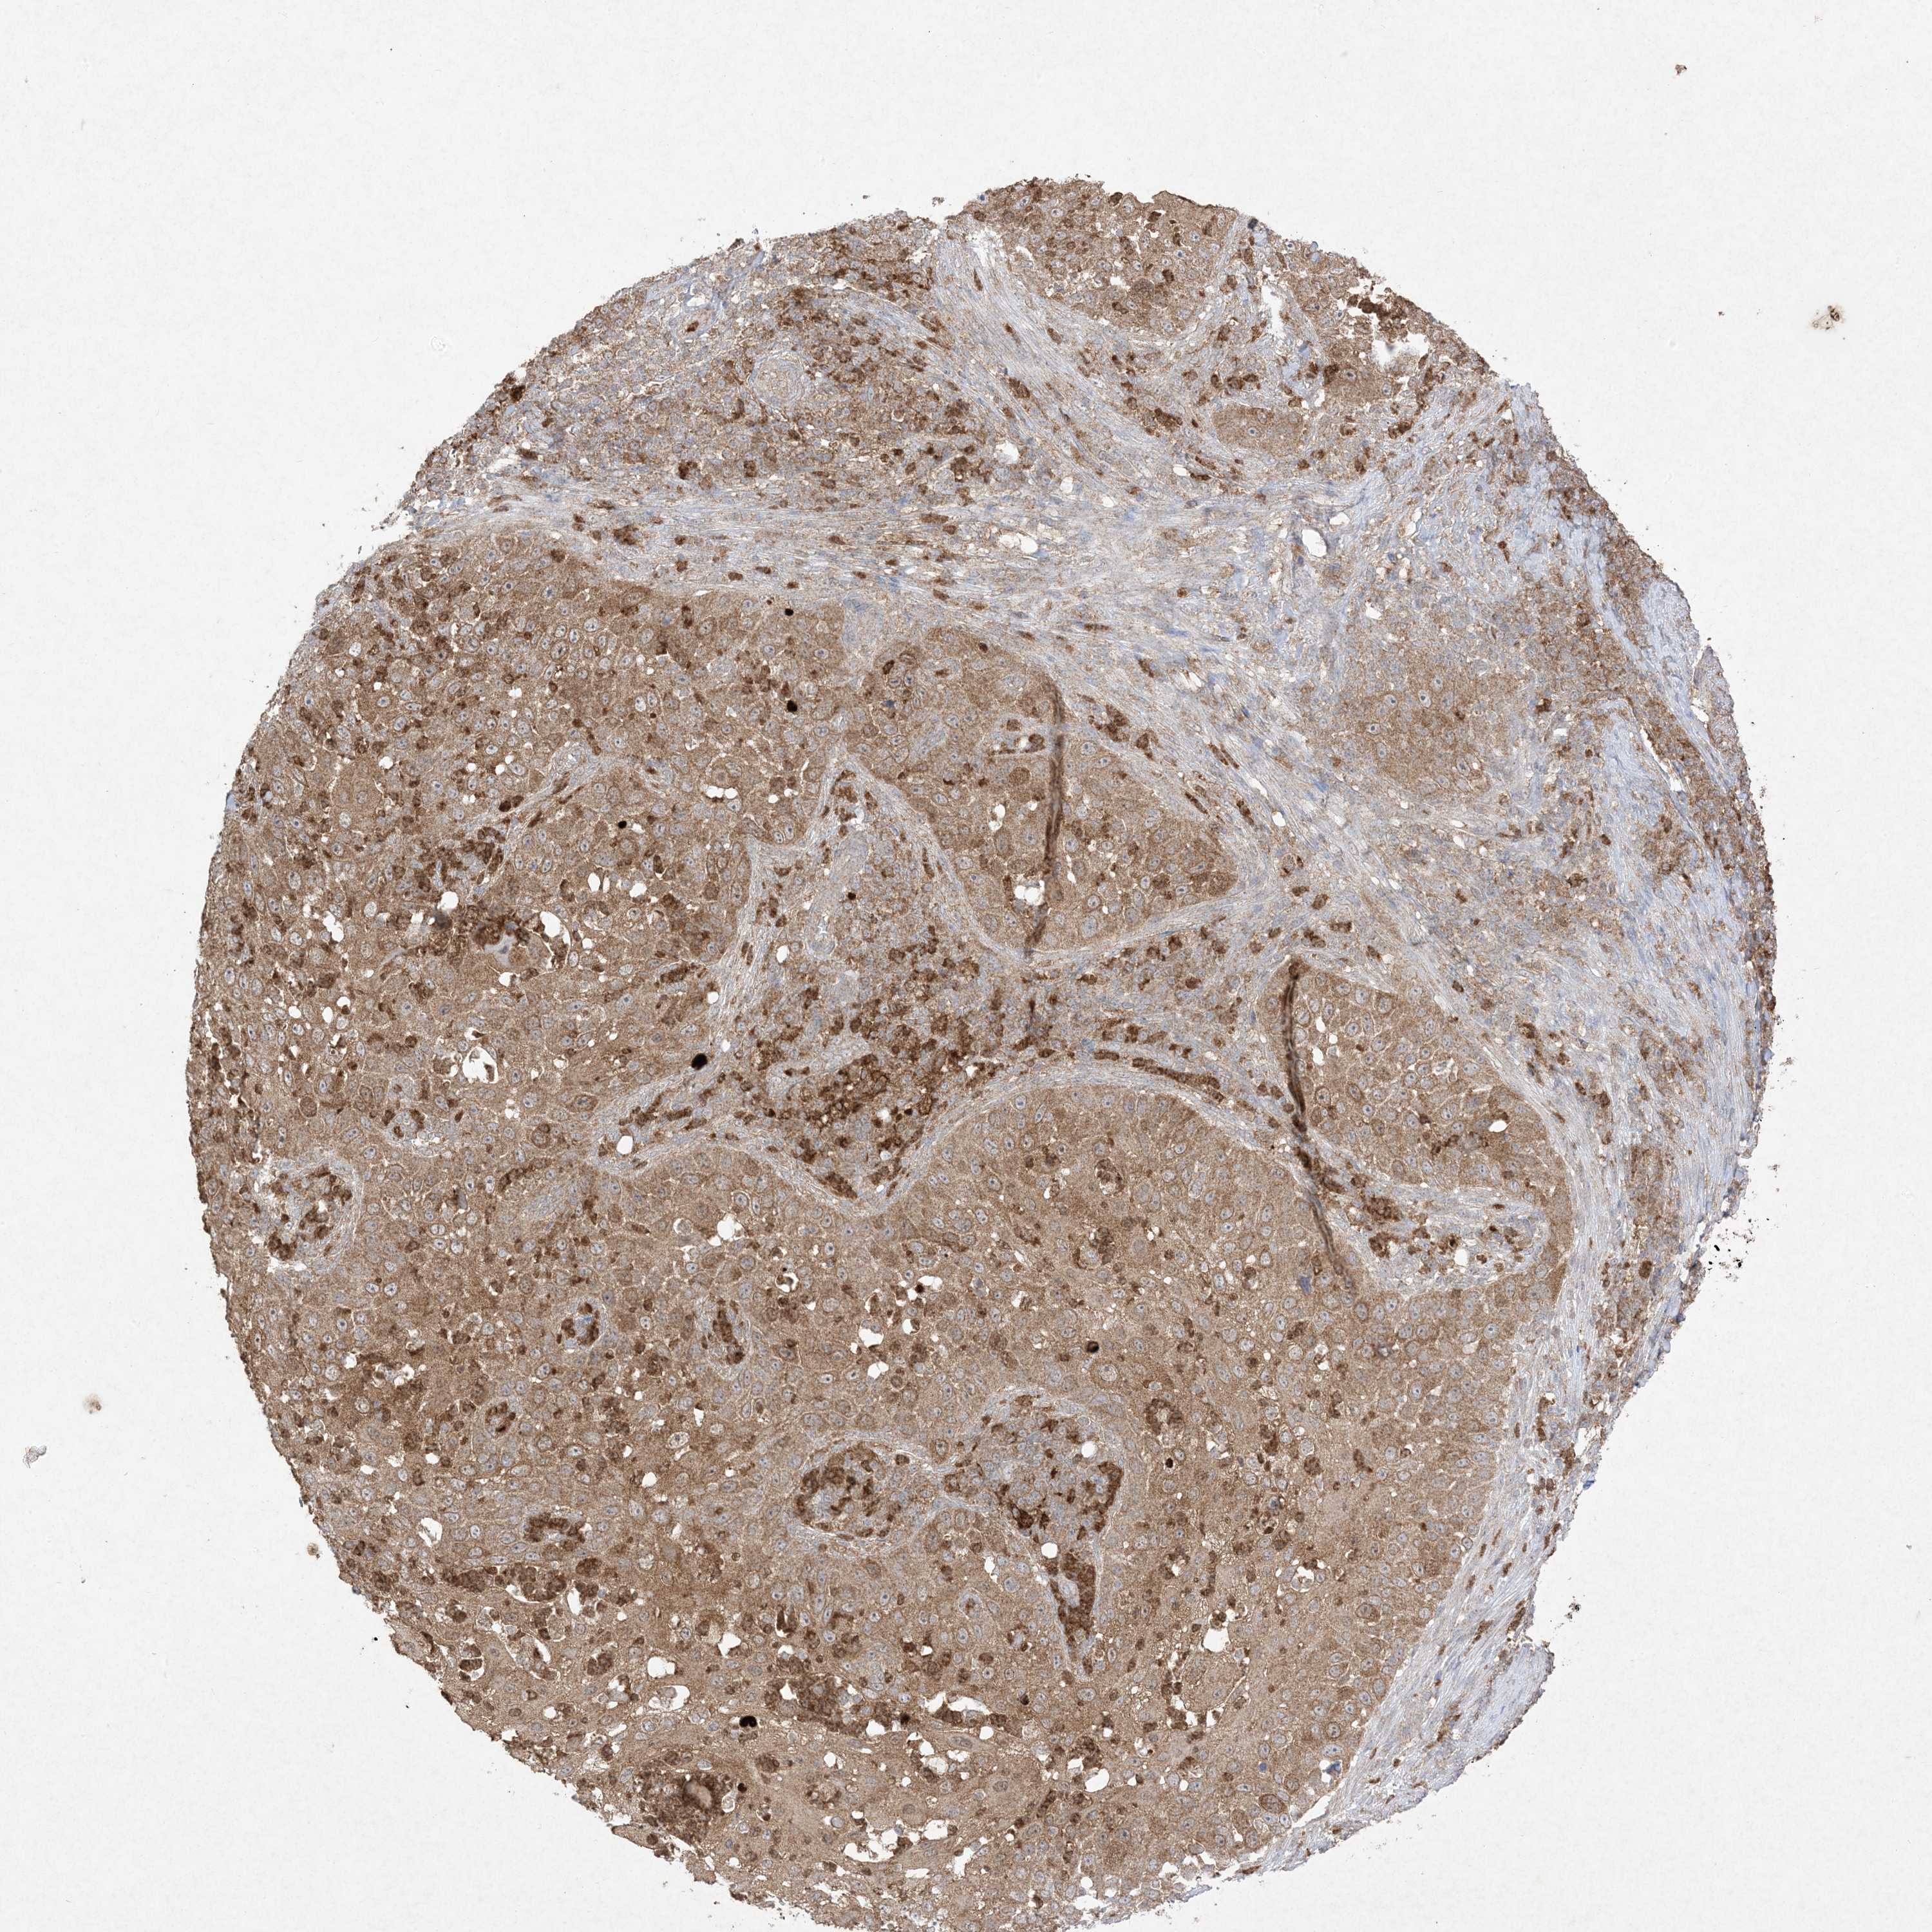

SKIN CANCER - Protein expressioni

A mouse-over function shows sample information and annotation data. Click on an image to view it in a full screen mode. Samples can be filtered based on level of antibody staining by selecting one or several of the following categories: high, medium, low and not detected. The assay and annotation is described here.

Each image is clickable and will lead to virtual microscopy that enables deeper exploration of all samples and also displays staining intensity scores, fraction scores and subcellular localization as well as patient and tissue information for each sample.

Antibody HPA054975

Antibody CAB011464

Antibody CAB035990

Antibody CAB080407

Staining

High

Medium

Low

Not detected

Basal cell carcinoma